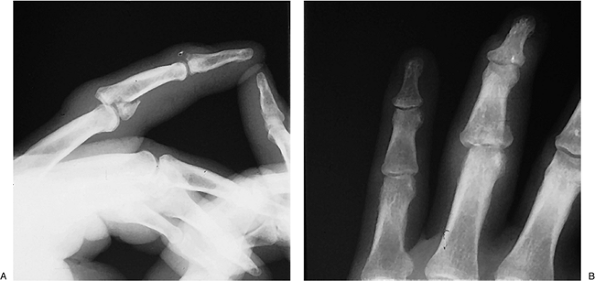

Figure 9-11 demonstrates a neglected oblique fracture of the proximal phalanx that healed with an articular offset and subsequent deformity. A realignment osteotomy corrected the deformity.

followed by protected early motion. Figure 9-12 demonstrates such a case.

Figure 9-12 An unstable fracture at the base of the proximal phalanx. A. Note the displaced and slightly comminuted fracture at the base of the proximal phalanx. B.

A single K-wire was used to fix the fragment to the phalanx, and a

longitudinal K-wire was used to stabilize the joint. The longitudinal

K-wire was removed at 3 weeks, and protected motion was started by

strapping the middle finger to the index finger. -